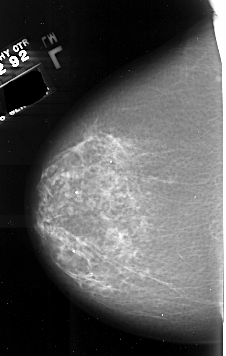

A_1008_1.LEFT_CC

LEFT_CC LINES 6406 PIXELS_PER_LINE 4066 BITS_PER_PIXEL 16 RESOLUTION 42 NON_OVERLAY